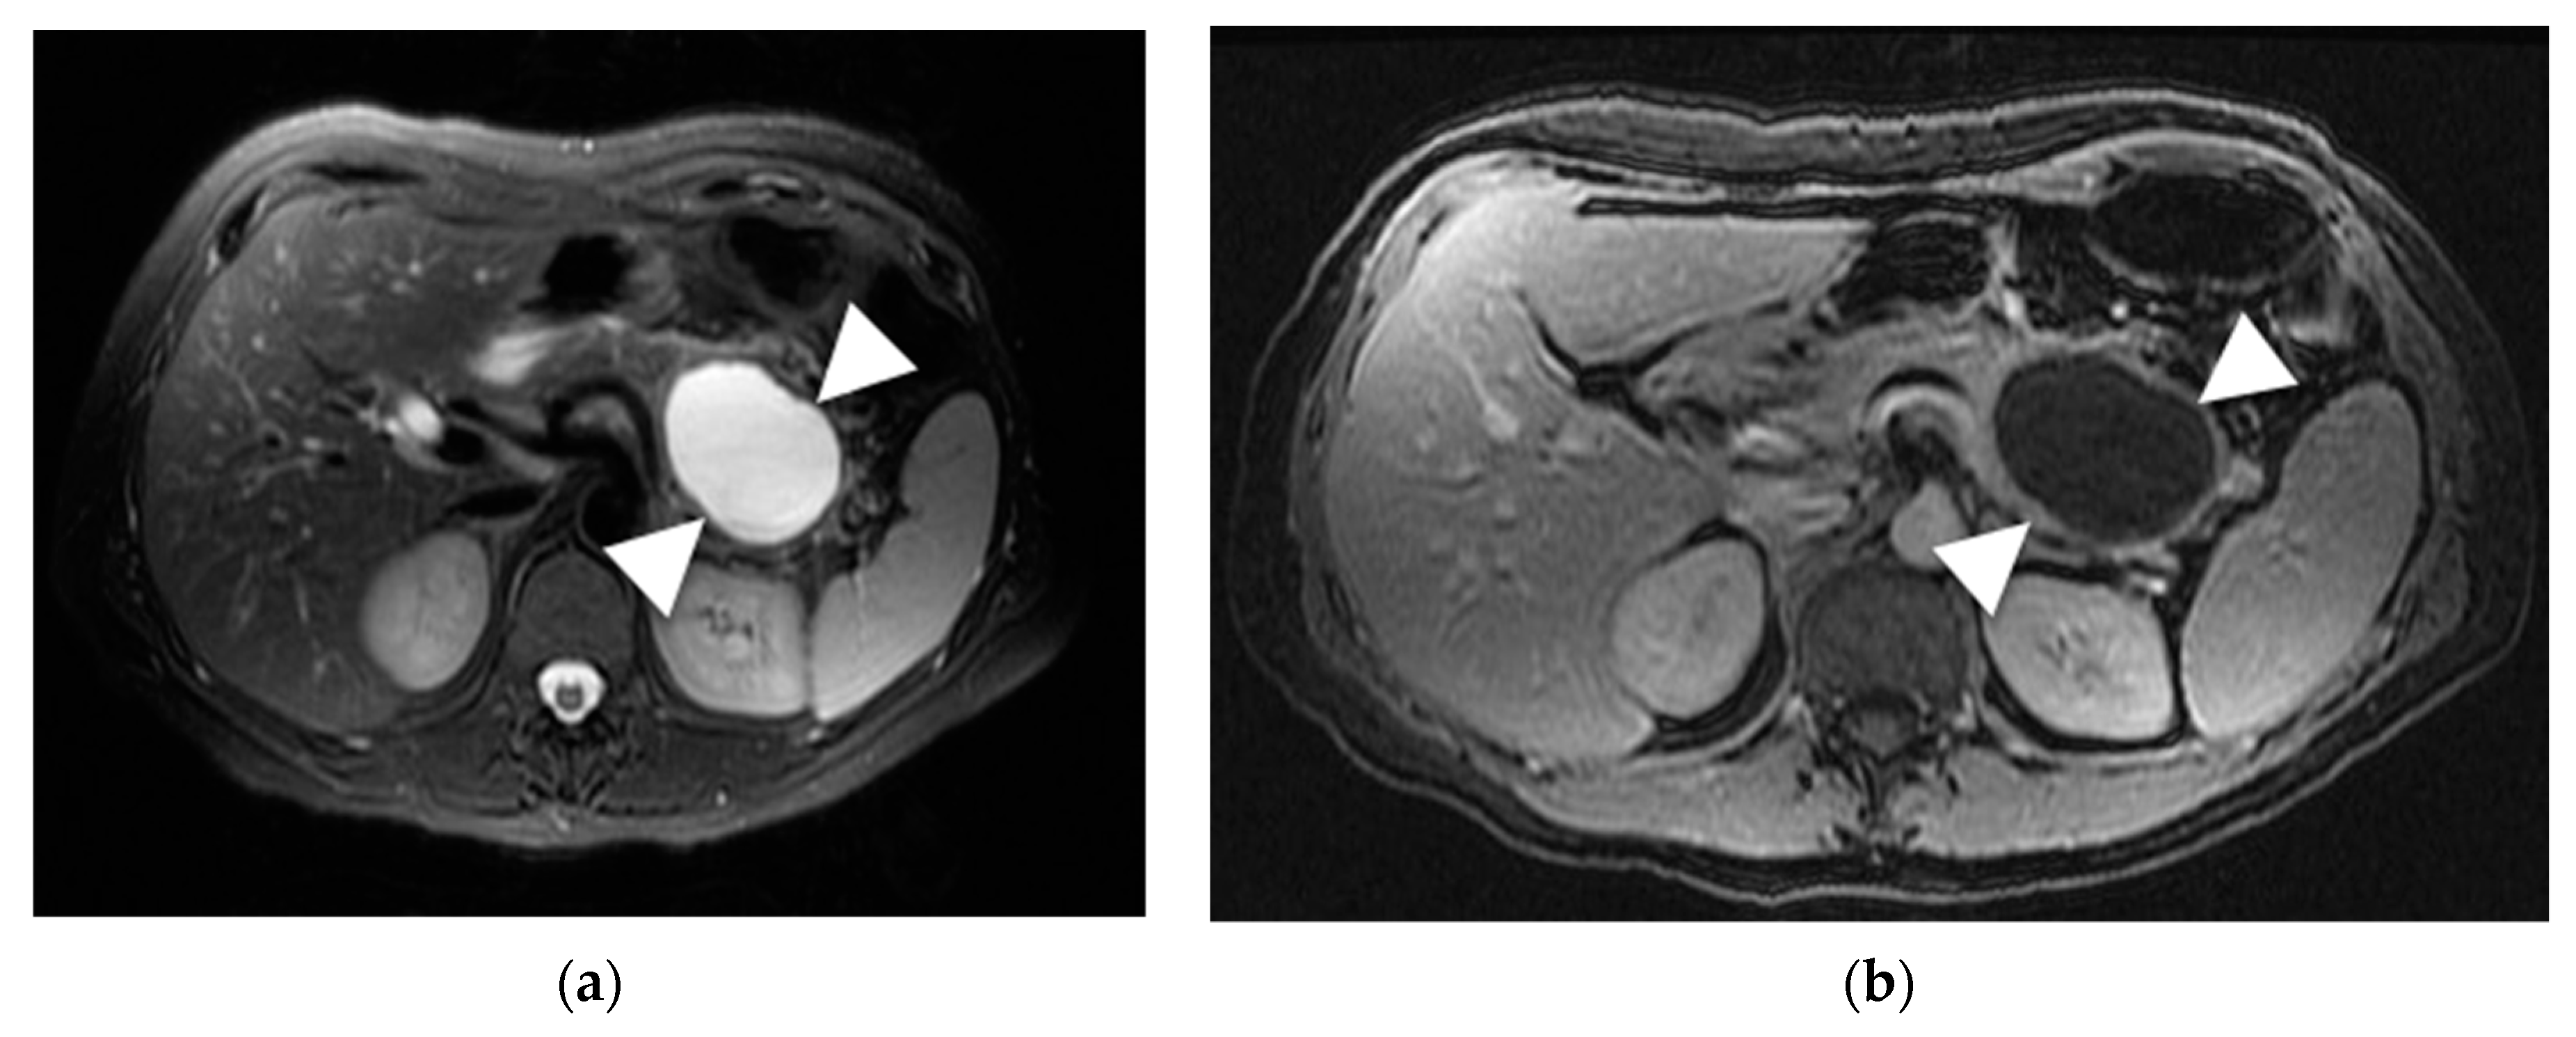

6.7. Solid Pseudopapillary Neoplasm (SPN)